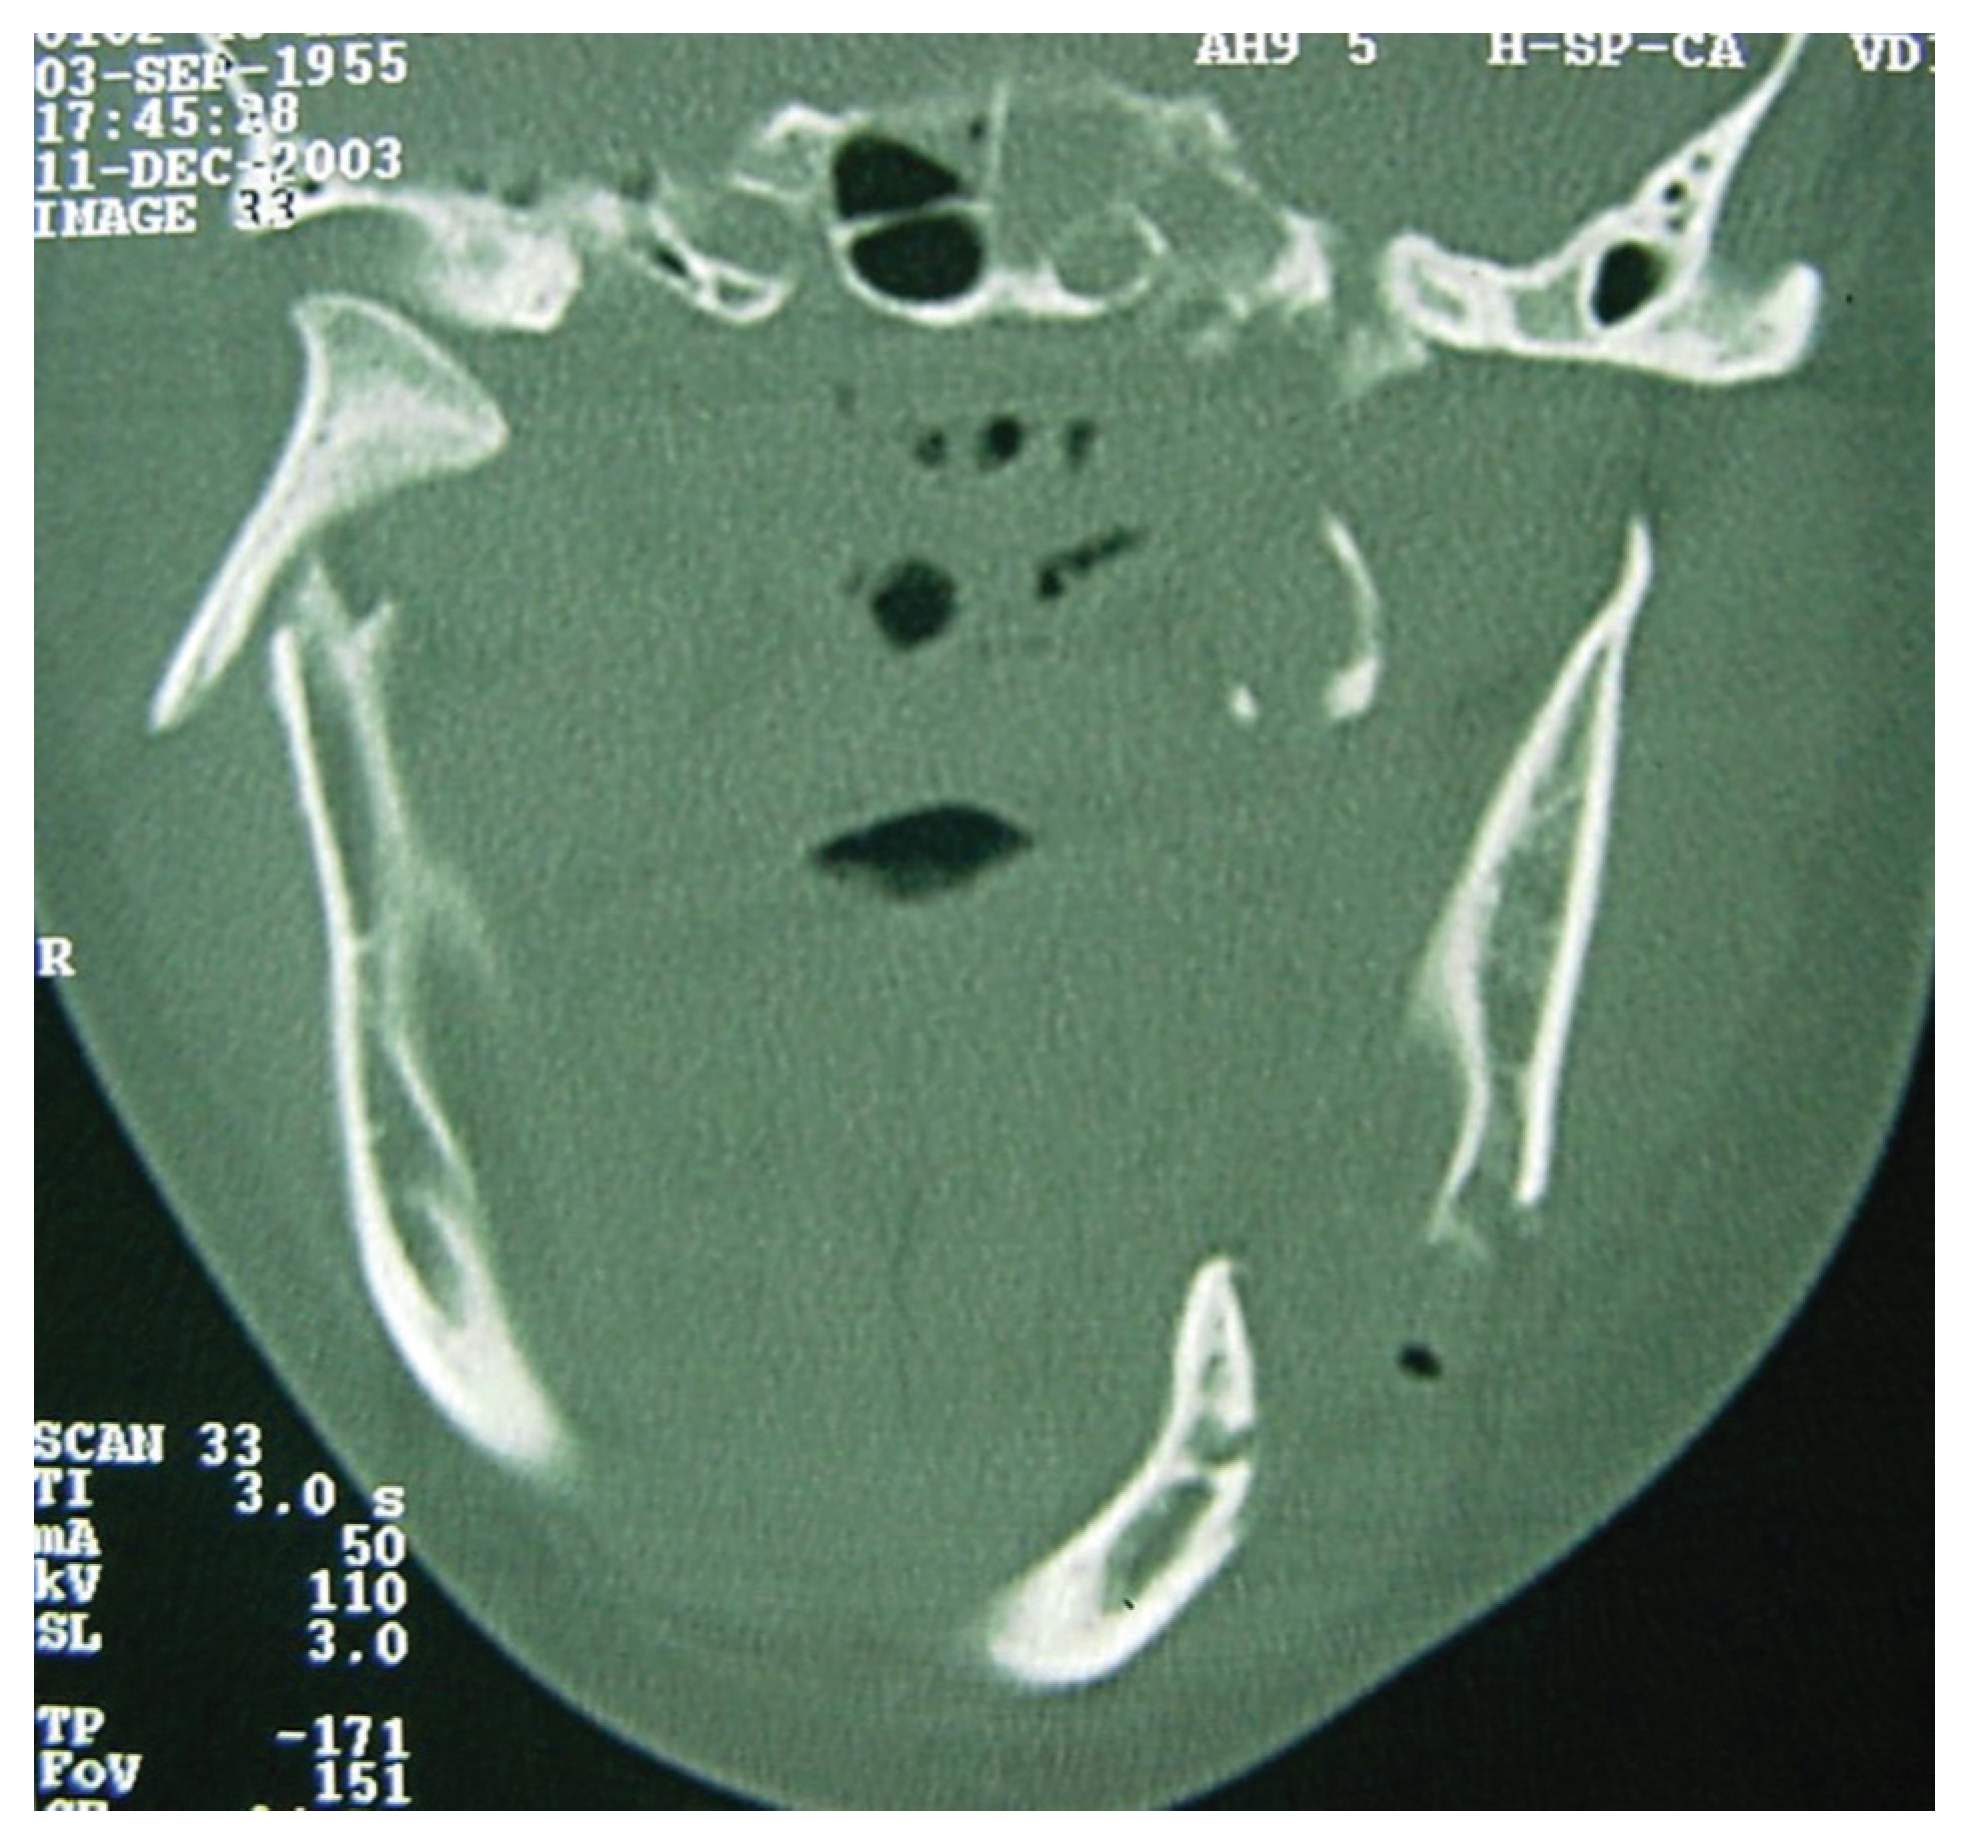

A computed tomography (CT) was performed in a fourchannel spiral CT scanner (Toshiba Asteion 4; Toshiba, Tokyo, Japan) with axial, coronal, and sagittal views. Multiple frac-tures were identified on the face (Figure 2 and Figure 3) and on the left side of the SS region (Figure 4).

Figure 3. CT windows displaying multiple fractures in the lower third of the face or mandibular region.

Cmtr 10 00011 g003

Figure 4. CT windows with arrows highlighting fractures to the sphenoidal sinus.

Cmtr 10 00011 g004